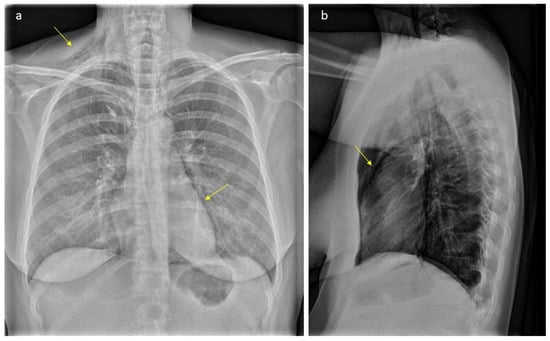

2. Case Presentation